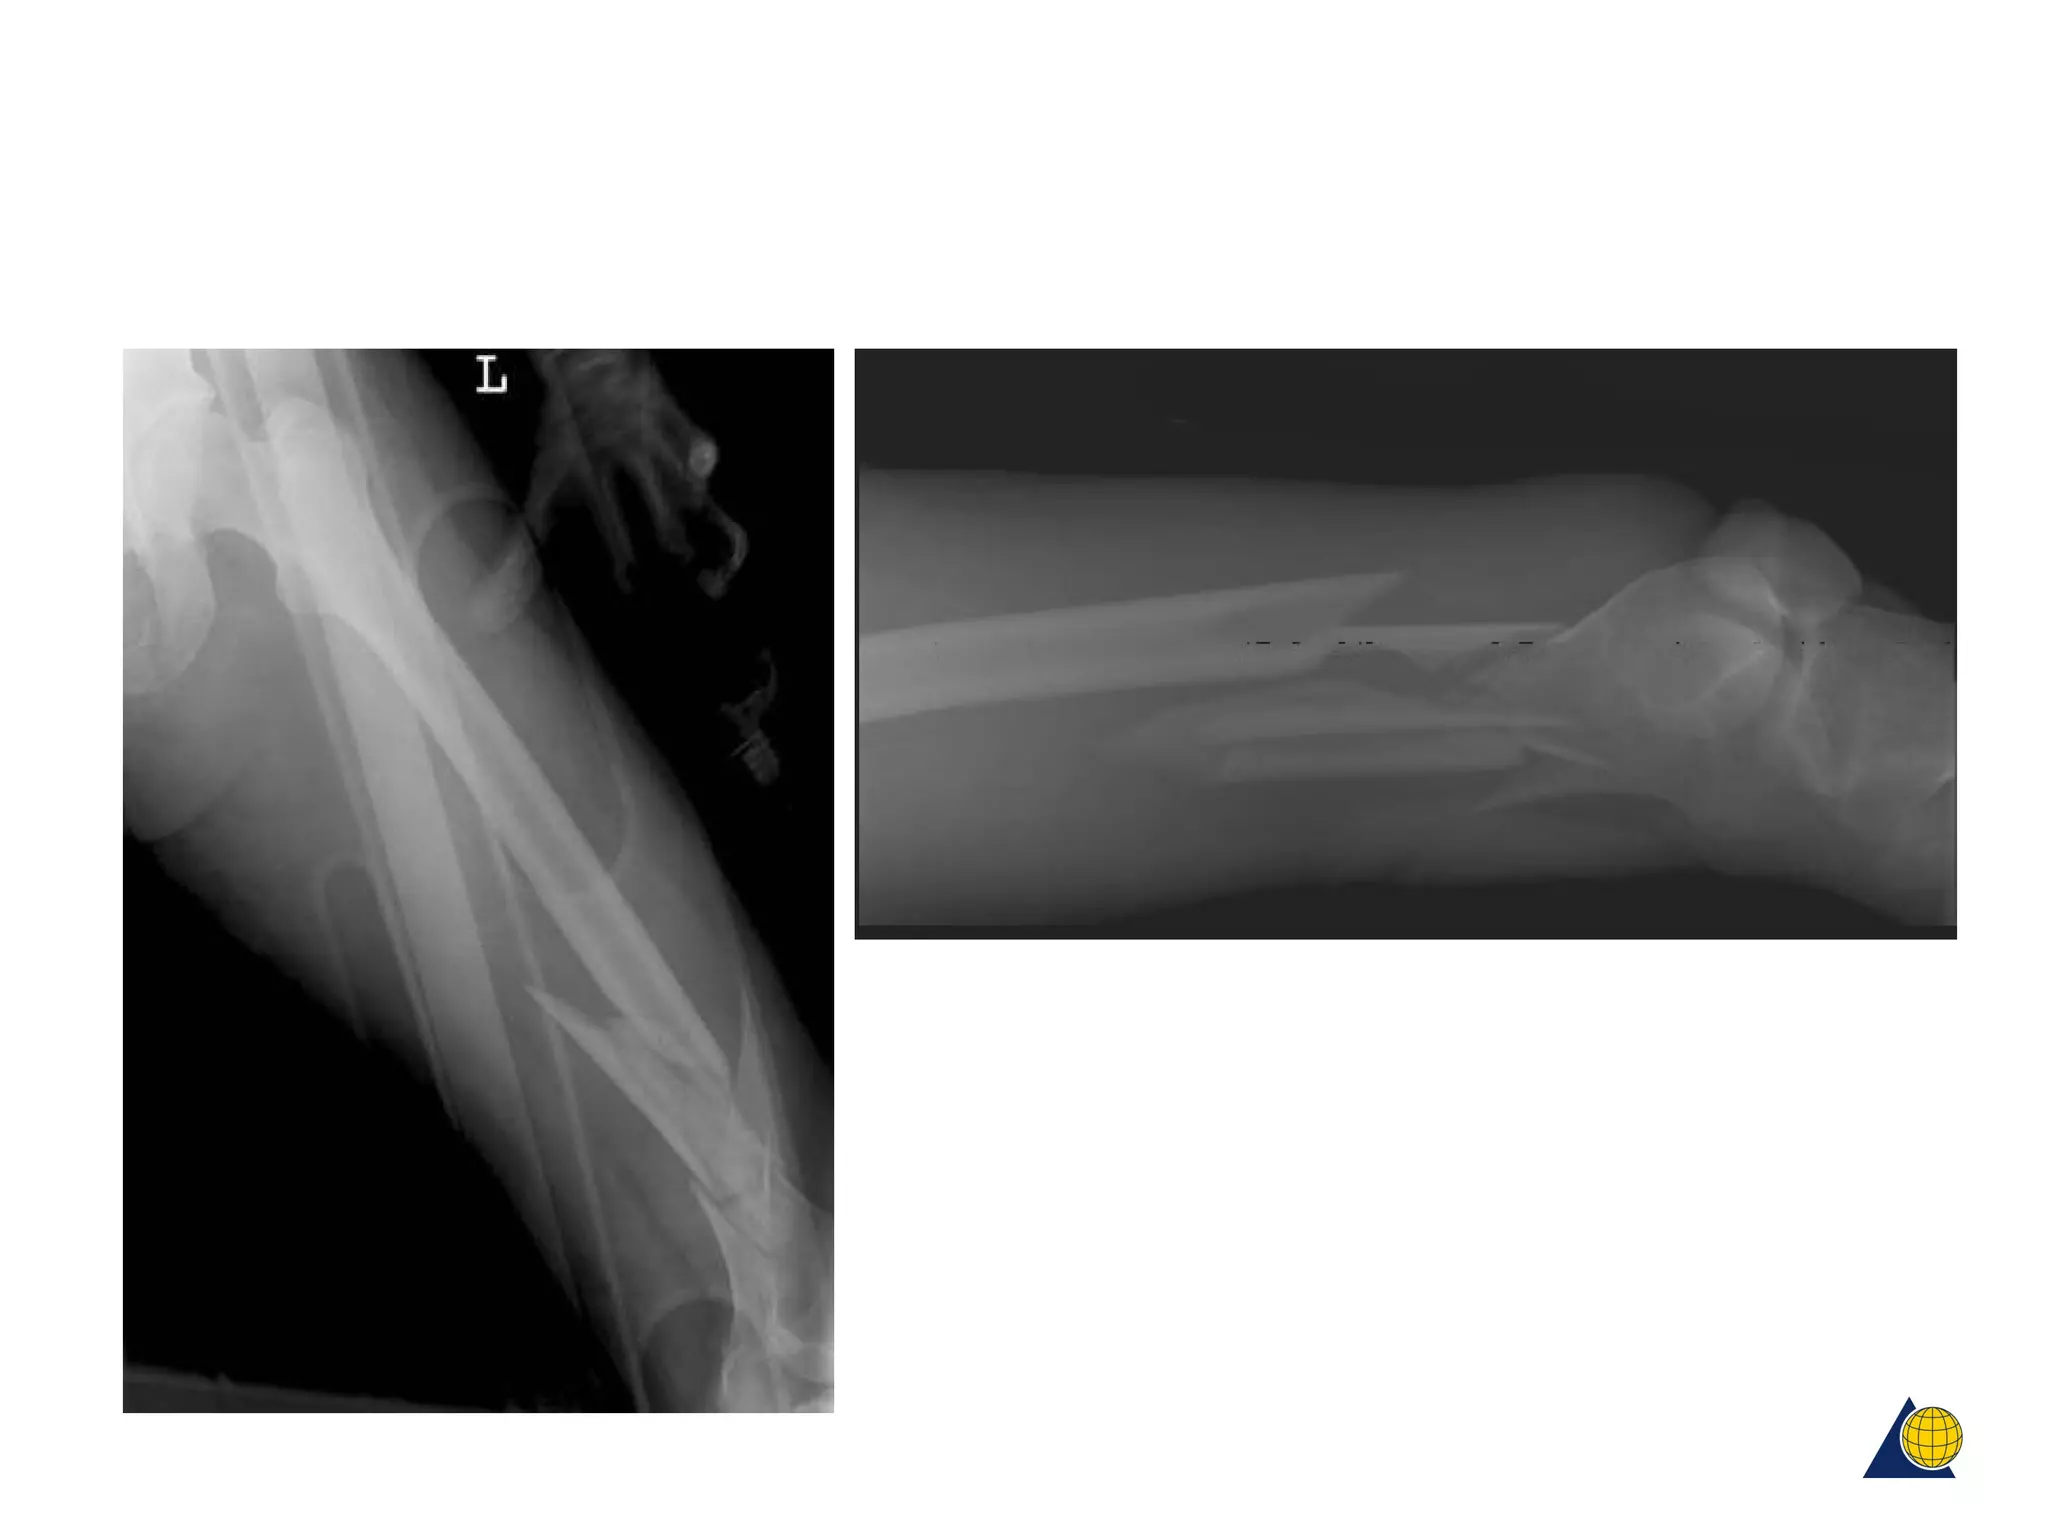

Case examples